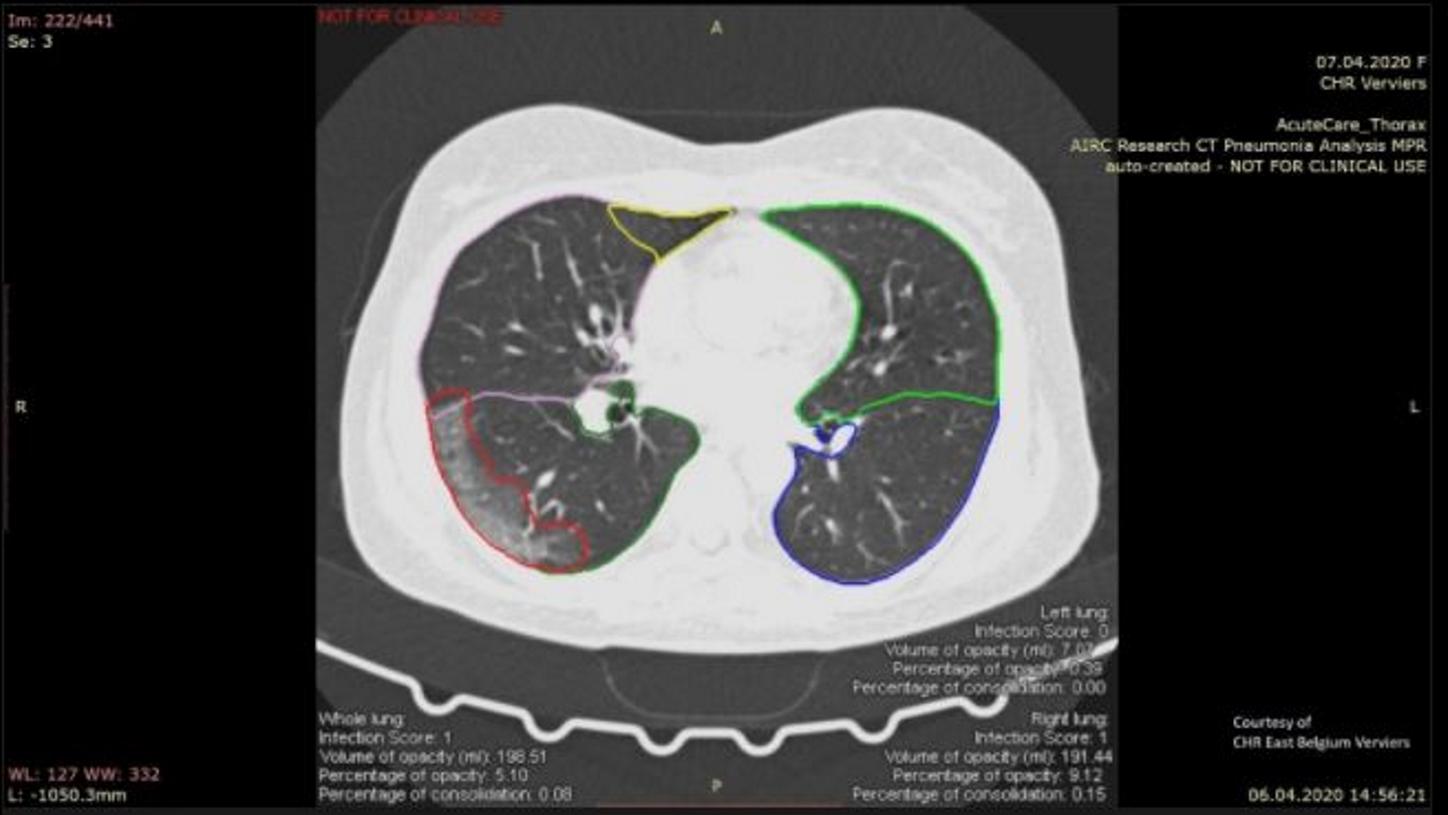

Leading AI scientist Bogdan Georgescu and his team have developed an algorithm that could greatly benefit clinicians in future by helping them to assess COVID-19 severity and progression.

Hot on the trail of COVID-19: Working with collaborators from around the world, a team began developing an algorithm that helps to evaluate changes in lung tissue. Read about how scientists reached a significant milestone during the pandemic.

Solutions that are based on artificial intelligence can ease the workload of radiologists by providing experts with analyses for further assessment. For radiology, this means greater efficiency.

3 Image created with Cinematic Rendering, Courtesy of CHR East Belgium Verviers